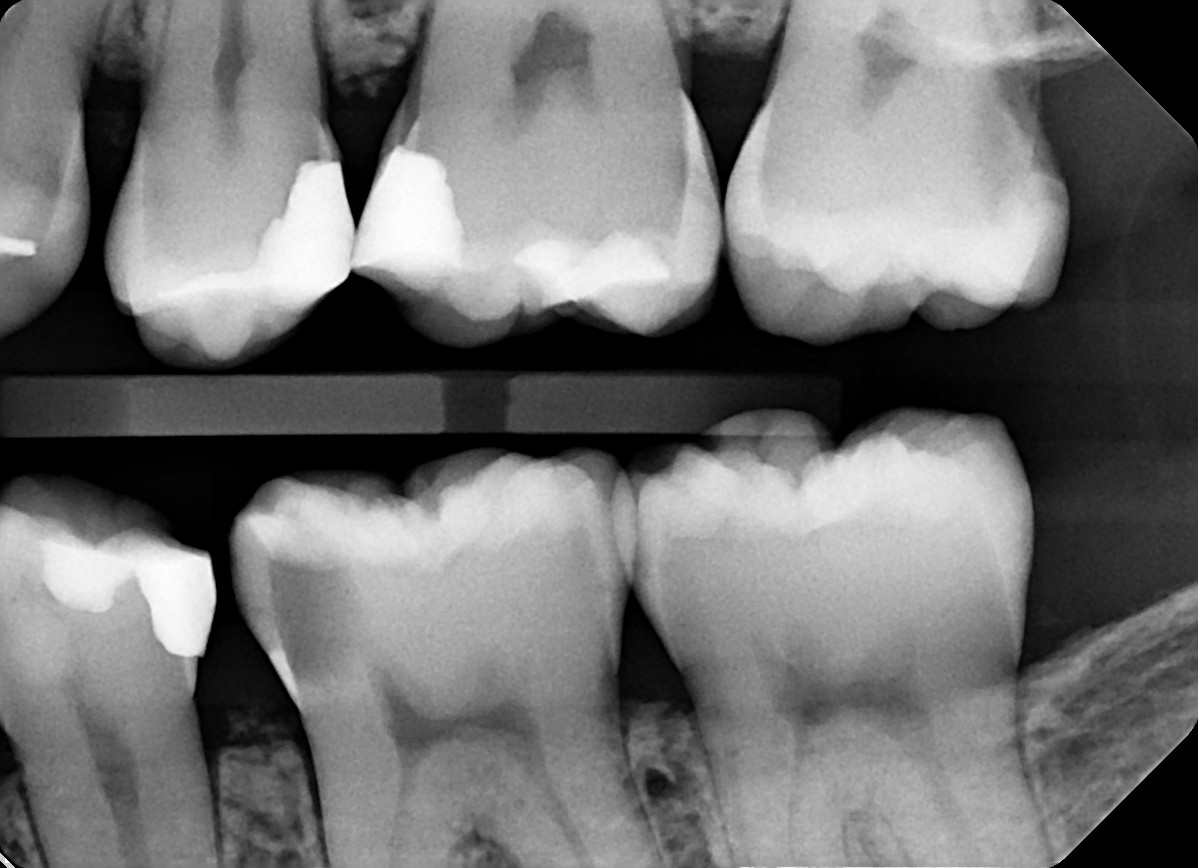

3 / 35

3. On which surface a recurrent caries can be detected?

mesial tooth # 3.7 is CBO

4 / 35

4. On which surface a recurrent caries can be detected?

distal tooth # 2.5 is bonding pooling